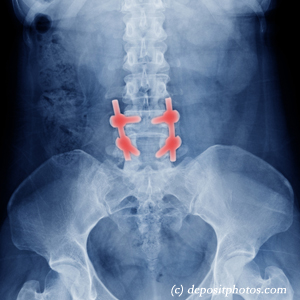

Persistent back pain following back surgery presents a significant challenge, with usual approaches often offering limited relief. Cox® Technic, a specialized form of chiropractic distraction spinal manipulation, offers a hopeful conservative treatment option. This gentle technique uses a specially designed table for controlled distraction treatment of the low back, creating decompression while mobilizing restricted segments.

Cox® Technic's effectiveness stems from its ability to generate negative intradiscal pressure, promote nutrient exchange, and restore normal spinal biomechanics without aggressive manipulation. This makes it particularly suitable for post-surgical patients needing gentle, precise treatment that respects altered spinal anatomy while addressing ongoing pain and dysfunction.